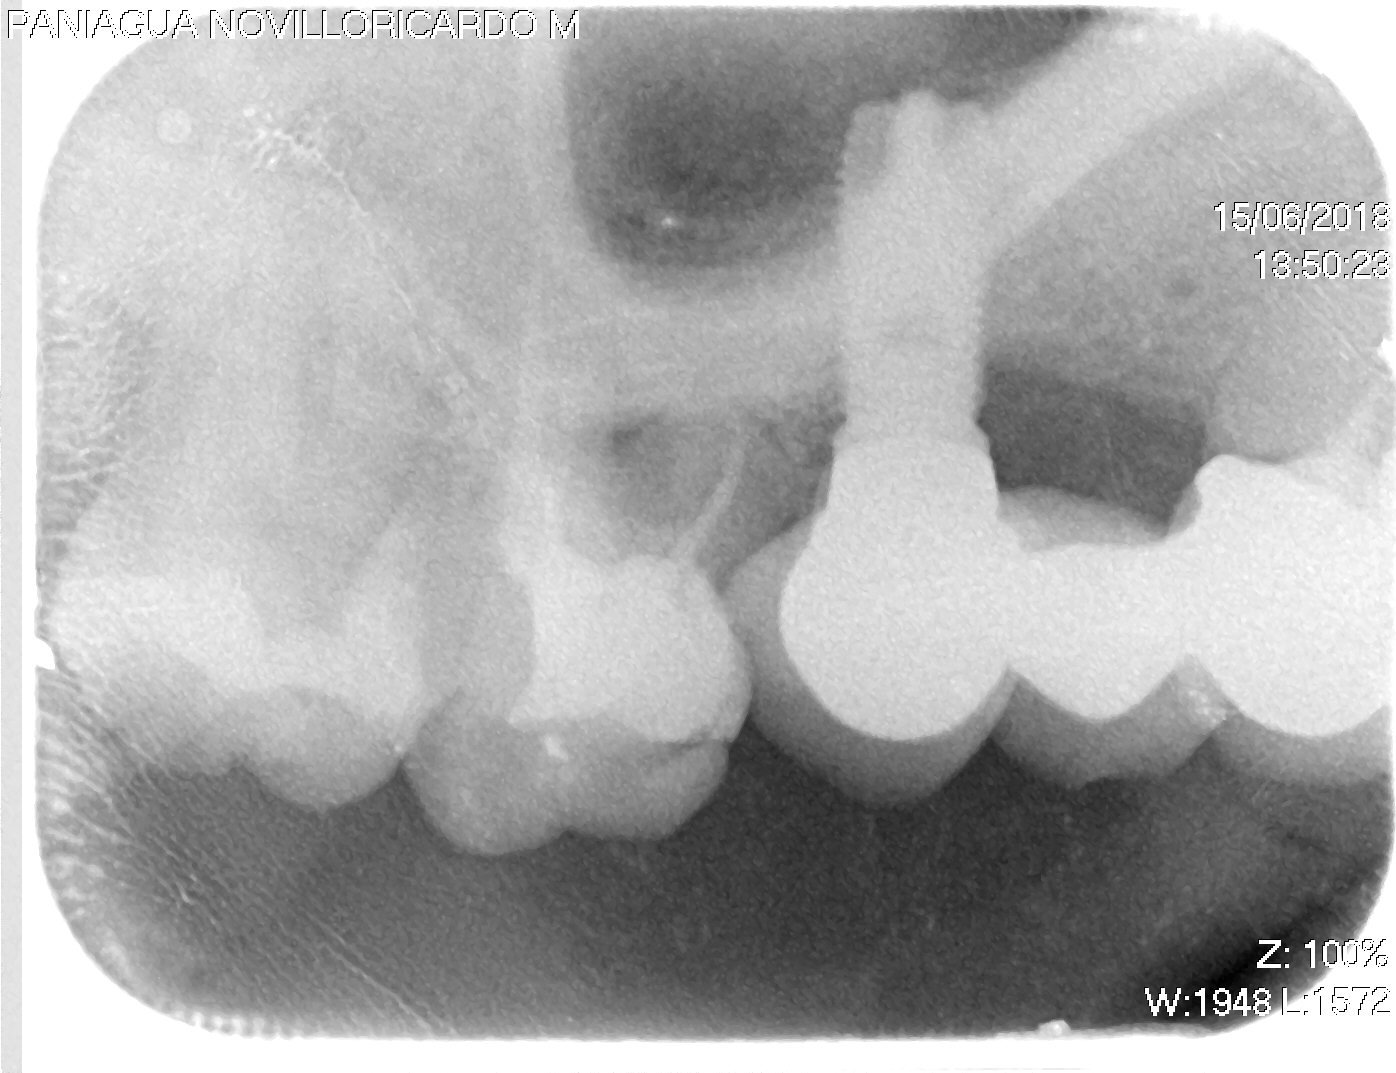

Mujer de 45 años, que acude a consulta con los implantes ya colocados. Quiere rehabilitarse, pero no se que marca, conexión... es. ¿Podrían ayudarme? muchísimas gracias.

Paciente rehabilitado con implantes y coronas en 22 y 14 hace unos años. No puede volver a la clínica donde se lo hicieron y no puede obtener información sobre los [...]

Es el implante en posición 14

Me podríais ayudar a identificar este implante ,gracias.